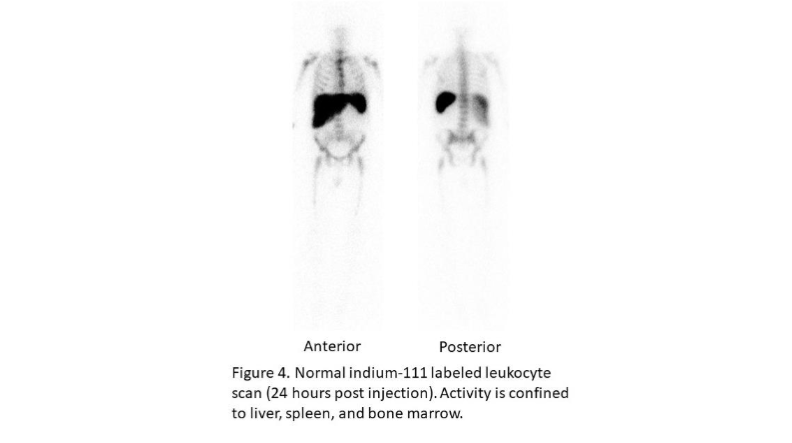

The in-vitro labeling of leukocytes, which takes about 3 hours, can be performed with either indium-111 oxine (¹¹¹In) or technetium-99m exametazime (⁹⁹ᵐTc). Each of these radionuclides has certain advantages, but ultimately the choice of which one to use is based on availability and personal preference. When cells are labeled with ¹¹¹In, imaging is performed 18–30 hours after infusion of labeled leukocytes, at which time the normal distribution of activity is limited to the liver, spleen and bone marrow (Figure 4)¹⁰.

Figure 4. Normal indium-111 labeled leukocyte scan (24 hours post injection). Activity is confined to liver, spleen, and bone marrow.